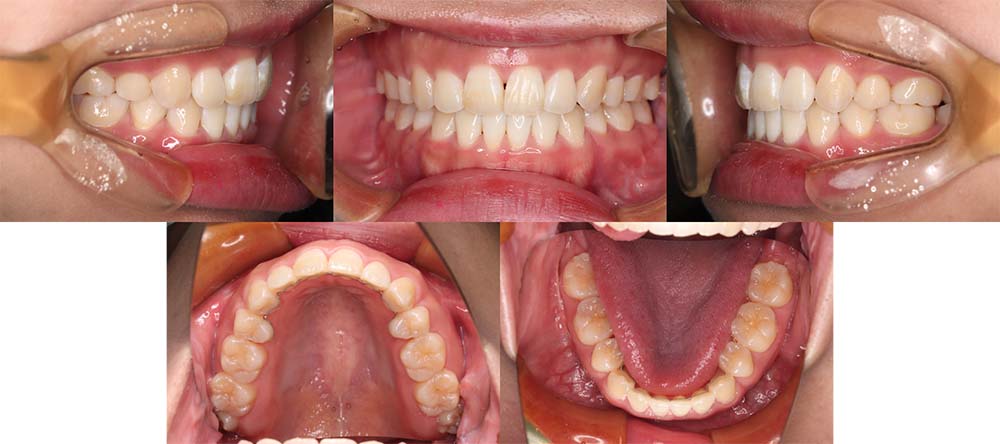

| 症例分類 | 顎変形症、叢生、下顎前突 |

| 診断名 | 下顎の左側偏位を伴う骨格性下顎前突 |

| 主訴 | 上下ガタガタ、受け口 |

|---|---|

| 年齢 | 15歳10ヶ月 |

| 性別 | 女性 |

| 抜歯部位 | 上の左右第一小臼歯 |

| 使用装置 | 表側のワイヤー装置+外科矯正(手術を併用した治療) |

| 治療期間 | 2年2ヶ月 |

| 保定装置 | 固定式保定装置、取り外し式保定装置(8時間) |

| 費用 |

保険適応 [検査・診断等] 2万円程度 [装置装着] 5〜7万円程度 [調整料] 2,000〜7,000円程度/回 [手術前検査等] 2万円程度 [保定装置等] 4万円程度 合計18〜25万円程度 |

骨格的に下顎が前方と左側に偏移しており矯正単独では治療が難しいため、上顎第一小臼歯を抜去して上下顎の手術を併用して治療することになりました。

1年7ヶ月の術前矯正後、上下顎の手術を行いました。

術後の顎間ゴムをしっかりと使用していただけたため、術後8ヶ月で治療が終了することができました。

下顎の前突感を改善することができました。